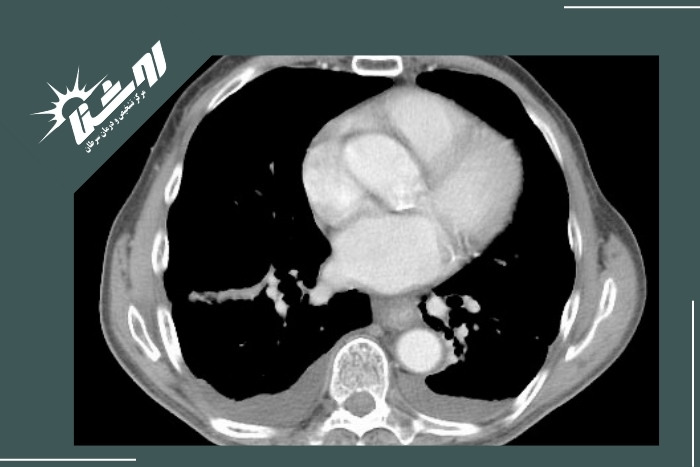

تشخیص آب آوردن ریه (پلورال افیوژن) با سونوگرافی

سونوگرافی قفسه سینه (اولتراسوند) یکی از بهترین ابزارها برای تشخیص وجود و میزان مایع در فضای پلور است. این روش با ارسال امواج صوتی با فرکانس بالا و دریافت بازتاب آنها تصویری زنده از ساختارهای داخل قفسه سینه ارائه میدهد. بهصورت خلاصه:

تشخیص نوع افیوژن (ساده یا پیچیده):

اگر درون مایع خطوط سپتوم یا ذرات معلق دیده شود احتمالاً افیوژن از نوع اگزوداتیو یا چرکی (امپیِما) است که نشانهی عفونت یا التهاب محسوب میشود.

به طور خلاصه اولتراسوند با ارائه تصویری زنده و دقیق از فضای پلور کمک میکند پزشک وجود، مقدار و نوع مایع اطراف ریه را شناسایی کند. این روش سریع، ایمن و مقرونبهصرفه است و امروزه در بیشتر مراکز درمانی به عنوان روش اصلی برای تشخیص آب آوردن ریه (پلورال افیوژن) مورد استفاده قرار میگیرد. اگر به دنبال یک سونوگرافی خوب در غرب تهران هستید میتوانید به مرکز تصویربرداری روشنا مراجعه کنید.